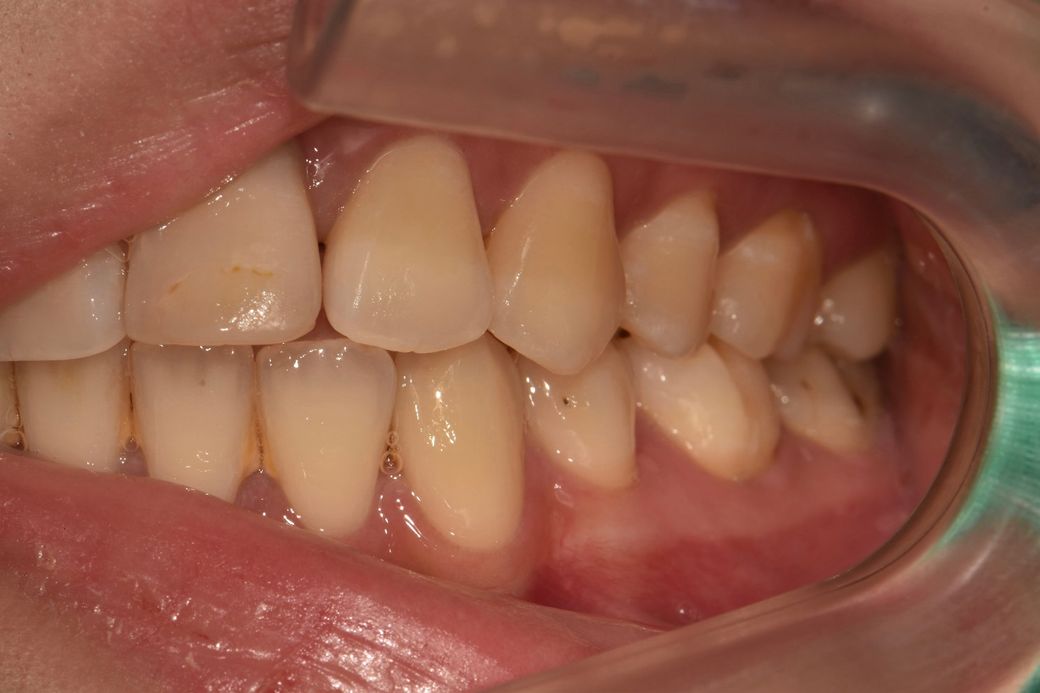

위에 쪽 앞니 하나 어금니 하나? 엑스레이 사진 찍어봤다는데 뭐가 뭔지 모르겠어서요 아마 첫번째 사진이 앞니같은데 신경치료 받아야할 정도인가요? 여기 선생님 말씀으로는 어금니는 충치가 좀 심해서 신경치료하고 크라운 씌워야한다 하셨고, 제 기준 오른쪽 앞니는 앞니 신경이 죽어있고 염증도 그래서 살짝 있다 육안으로 봤을 때도 앞니 두개 색상차이가 좀 난다 그래서 신경치료 몇회하고 크라운 해야한다 하셨는데 전 솔직히 거울 보면서 앞니 색상은 분간이 안돼서… 살면서 특별히 느낀 통증도 없었어요 참고로 신경 죽어있다는 앞니는 제가 정말 어렸을 때 깨진거고 그대로 두고 살다가 고등학생때 교정마치고 깨진부분 붙힌겁니다 세번째 사진 보시다시피 붙힌 라인에 노랗게 뭐가 낀거 마냥 변해있구요 일반 치아 마지막 사진은 윗니로 추정되는 것을 올리는 겁니다 제가 지금 윗니 교정장치가 떠서요 여기를 의심하는 건 아니고 다른 치과 의사분들 의견이 궁금합니다 추가질문 더더 하셔도 돼요 신경치료 무서워요… 대충 달지 말아주세요ㅠ 진지하게 봐주셨음 합니다

1. 신경이 괴사된 치아는 조금씩 검게 변하기도 합니다 앞니는 색 변색도 보이고, 탈구되었던 흔적도 보이네요 신경치료는 불가피할것 같습니다